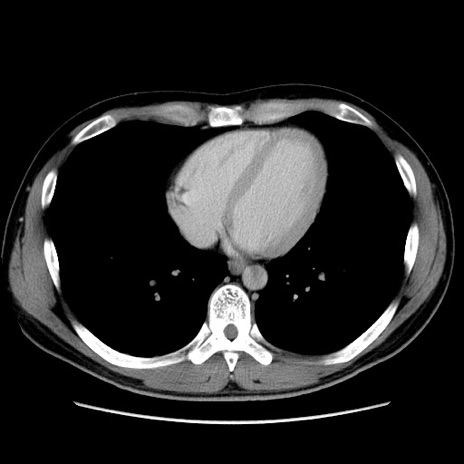

症例36(横断像)

冠状断像

【症例】20歳代 男性

【主訴】心窩部痛

【現病歴】今朝より上腹部痛あり。一旦軽快していたが再度出現したため救急要請。昨日夕に白身の魚を含む刺身を食べた。

【身体所見】BP 136/89mmHg、HR 74/min、BT 37.0℃、腹部:膨満、軟、心窩部に圧痛あり。反跳痛なし、筋性防御なし、腸雑音やや亢進あり。

【データ】WBC 17700、CRP 0.48